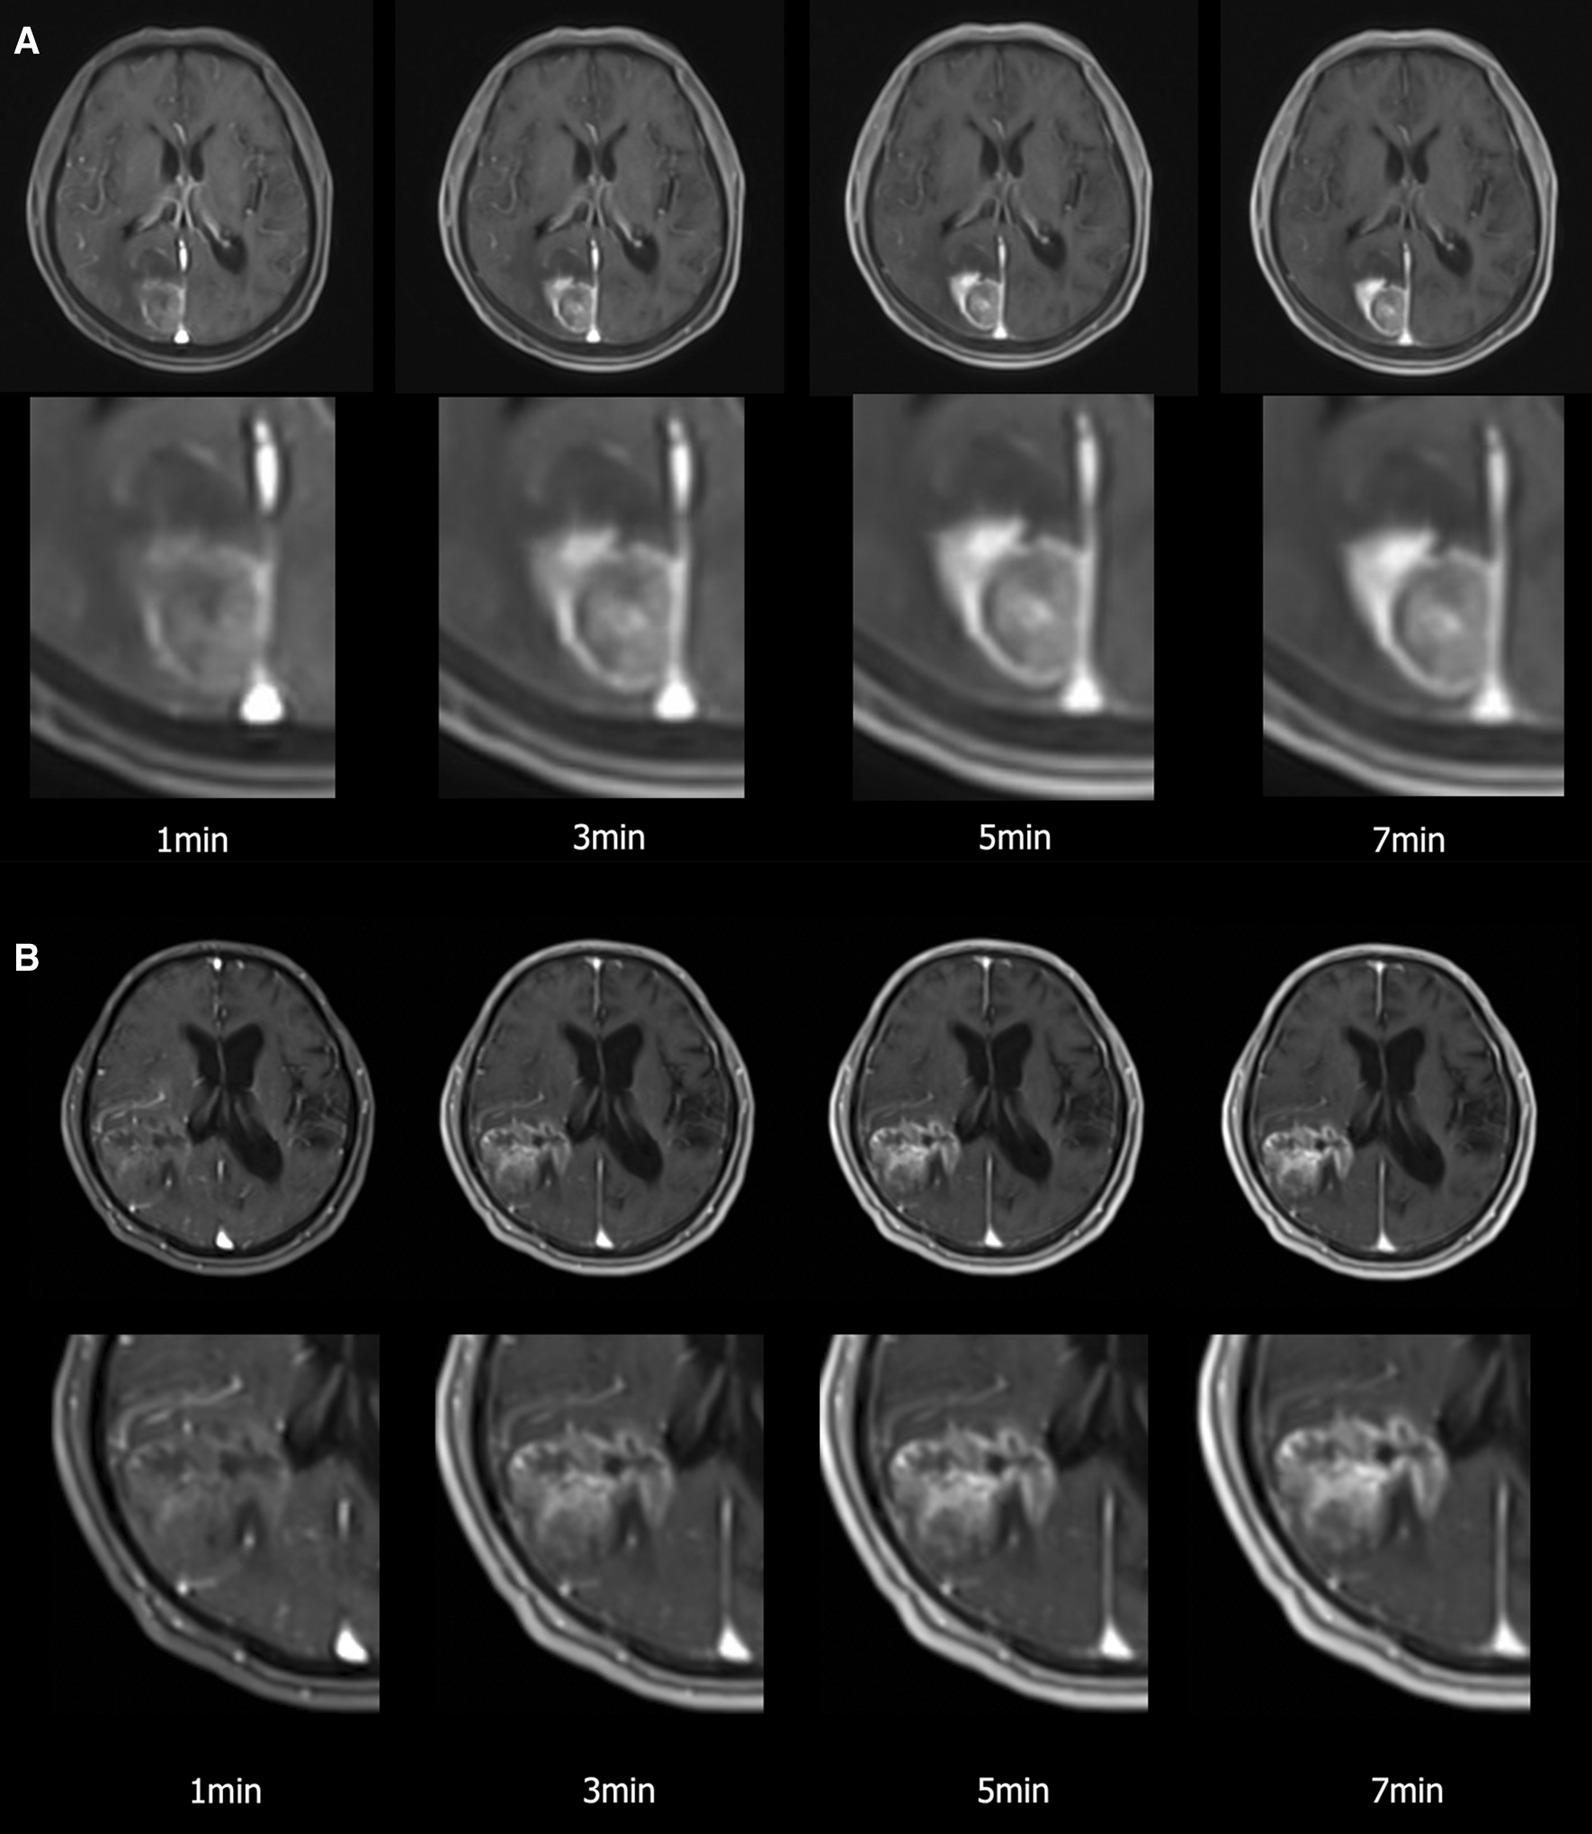

In this study, we found that the maximum TTP of brain metastases, primary brain tumors, and meningiomas was approximately 5 min. Qualitative and quantitative assessments of contrast enhancement supported this finding, showing that images acquired 5 and 7 min after contrast agent injection were comparable in terms of lesion conspicuity and enhancement (Fig. 5). Enhancement on images acquired after 7 min was only marginally better for the longest diameter measurement of the lesions.

Fig. 5.

a A 69-year-old man displaying a brain metastasis from a lung cancer. 3D dynamic contrast enhanced (DCE) axial images acquired 1, 3, 5, and 7 min after injection of a single standard gadobutrol dose. The lesion on images acquired after 5 and 7 min appears similar in terms of conspicuity. b A 77-year-old man or woman displaying a primary brain tumor (glioblastoma). The lesion shows gradual increment of contrast enhancement that reaches the highest conspicuity 7 min after contrast agent injection